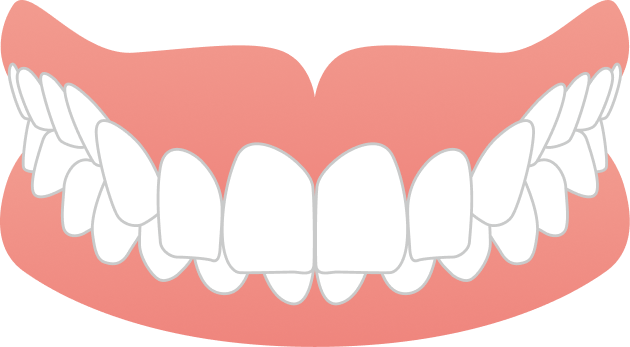

治療後は

・前歯でしっかり噛める噛み合わせ

・横顔の印象が整った美しい口元

・ホワイトニングによって洗練された白い歯

を手に入れられました。

AFTER